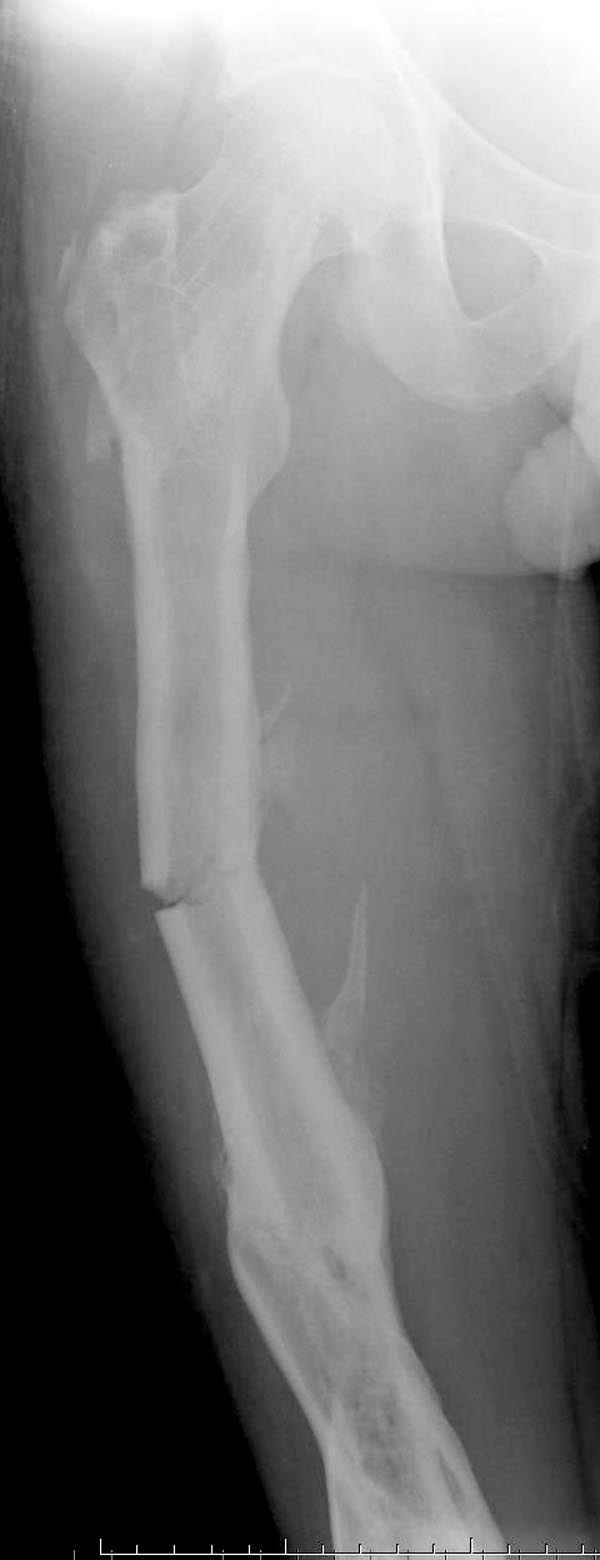

Инфекция канала и стрессовый перелом:

Представляю снимки больного с политравмой: леченного в другом мед.учреждении по поводу открытого перелома бедра, сперва аппаратом наружной фиксации, затем пластиной. Обратился к нам через 8 месяцев после удаления пластины с проблемой несросщего перелома бедренной кости, без клинических проявлении к инфицированию (не все снимки сохранены)

Рутинный интрамедуллярный остеосинтез с расверливанием и с фиксацией реконструктивным трокантерик штифтом (рис №1, №2),

если первые 4 месяца послеоперационного периода проходил без проблем, но на 5 месяце появились боли в дистальном отделе бедра и температура, т.е. симптомы медуллярного инфицирования (рис №3, №4).

Замена реконструктивного штифта “Custom made Nail” с антибиотиком (рис №5, №6),

после промывки канала с рассверливанием внутреннего кортекса, через 4 недели антибиотический штифт удалили, оспалителный процесс остановлен и бедро сросся.

Мы не дождались “Happy End”, у больного IQ в пределах 70%, через 6 месяцев вернулся после небольшой травмы, споткнувшись получил перелом

того же бедра (рис №7).

На следующий день произвели интрамедуллярный остеосинтез: этапы во время операции (рис №8, №9)

и последующих снимках (рис №10, 11, 12, 13) перелом сростается и передвигается с полной нагрузкой.

При обзоре причин перелома, на снимке №2 обнаружили, что один из стержней аппарата наружной фиксации проходил только через передний кортекальный слой, что создало стрессовую зону на бедре и в результате перелом из-за незначительной травмы.